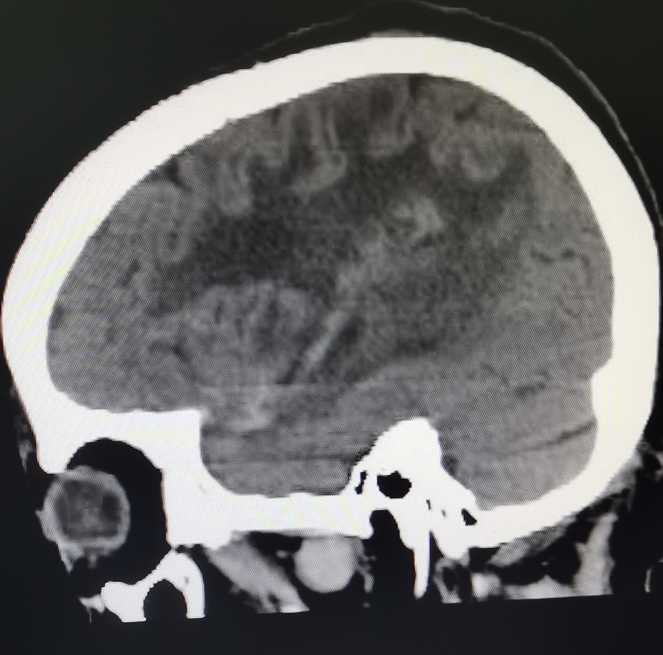

62岁的陈先生于今年曾因偏瘫在外院住院治疗无好转,且症状不断加重,甚至出现言语不清,小便失禁等异常。经影像检查(见图1)提示为左颞叶基底节区脑肿瘤,约6cm*5cm*5cm大小,比鹅蛋还要大,肿瘤位置深,向前累及外侧裂,包裹外侧裂部分血管,向下累及基底节区,肿瘤血供丰富,必须尽早实施手术治疗。

术前影像资料及手术标本,术前见中线结构严重偏移,侧脑室受压缩小,肿瘤周围水肿严重,肿瘤血供丰富

“由于肿瘤的位置侵犯外侧裂,影像学确定肿瘤包裹外侧裂的分支血管,有大脑中动脉以及枕动脉的多分支供血,紧邻肿瘤的还有过路血管。被包裹大的过路血管是不能损伤的,术中不小心损伤这段血管的话,大脑就会出现梗塞等一系列的并发症。”刘建民表示。